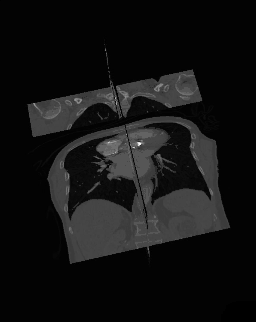

- 3D Multi-Planar Reconstruction

- A final variant on the MPR theme is the generation of a three-dimensional display showing all three orthogonal projections combined so that a defined point of interest locates the intersection of the planes, as illustrated in the following figure:

- The point of intersection is located for illustrative purposes at the centre of the voxel data in the figure above. It can typically be placed at any point in the 3D data using interactive controls. In addition, the perspective used for the rotating sequence can typically be manipulated interactively to improve the visualization of a region of interest. Note that the image sequence illustrated above is one from a myriad of perspectives that can thus be generated. Note also that slice projections (e.g. MIPs) can be combined with this form of display to provide additional perspectives on a feature of interest.